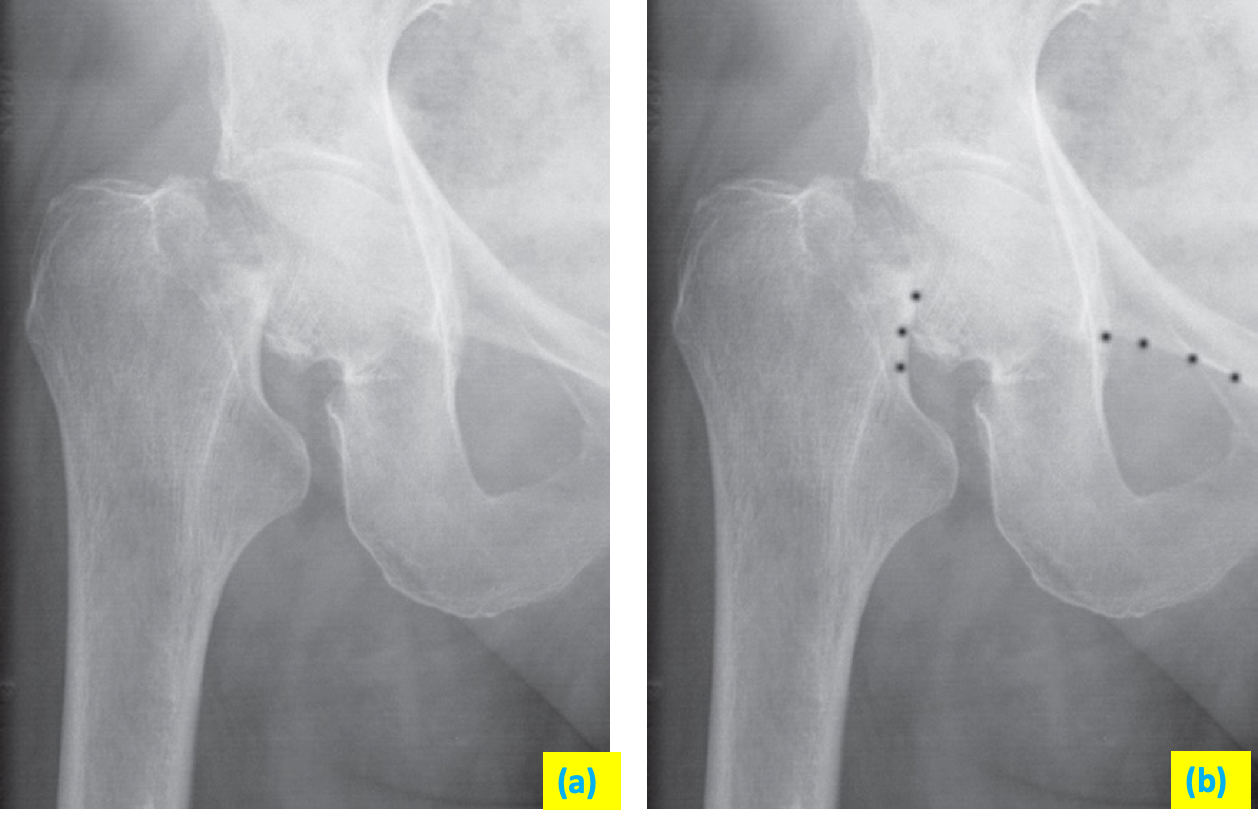

Fractures through the femoral neck Z Z are common in the elderly and may result from minor trauma. The radiographic signs in some instances may be subtle.

(a) A fracture through the femoral neck interrupts Shenton’s line. z

(b) Shenton’s line Z is a curved line formed by the top of the obturator ring and the medial aspect of the neck of the femur (the interruption of Shenton’s line is shown by the dots).